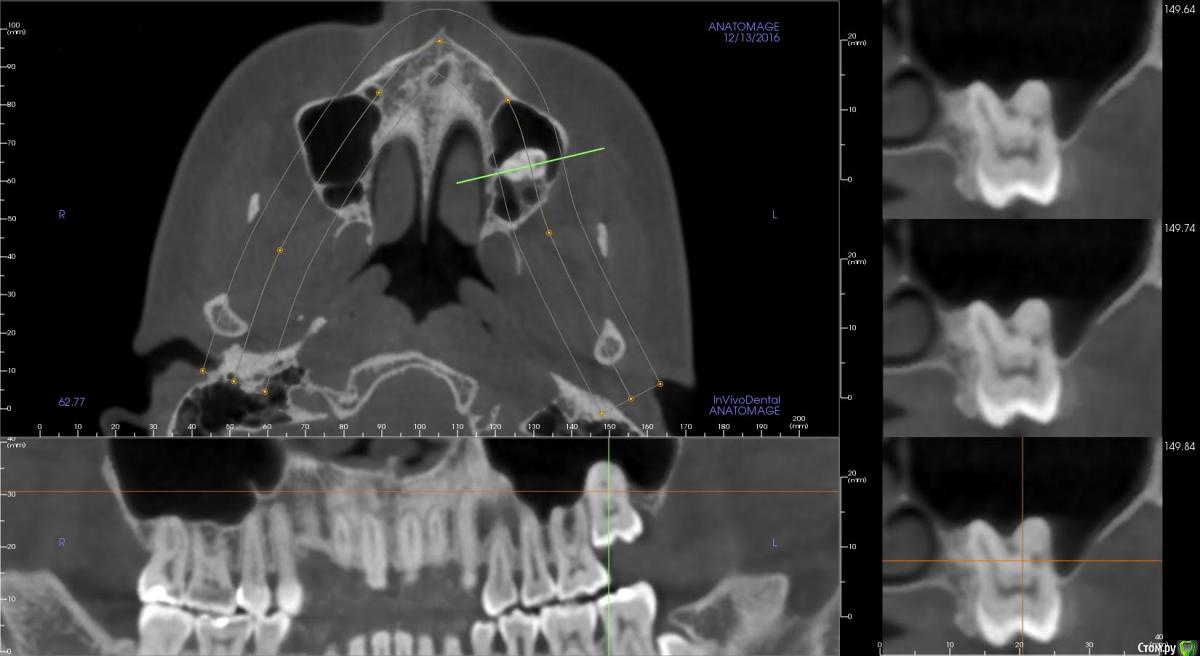

sus Опубликовано 13 декабря, 2016 Поделиться Опубликовано 13 декабря, 2016 (изменено) Здравствуйте, уважаемые специалисты! Пожалуйста, помогите принять решение, хирургия назначена на пятницу. Возраст - 32. Имеется импактированная семерка, которую сейчас хотим удалить. Раньше надеялись, что она спустится сама после удаления восьмерки в 2012 (она еще есть на первом, старом, фото), плюс поможем брекетами. За это время она сама так и не спустилась, так что ортодонт и хирург предположили анкилоз и отсутствие возможности вытянуть ее, даже сломав "мостики" и потянув брекетами. Единственная причина удаления - это торчащий над слизистой кусочек коронки, и, соответственно, в перспективе риск инфицирования через карманы вокруг. По томограмме, наверное, видно, что сам зуб пока вроде здоров (а торчит он так уже лет двадцать). Только что сделали томограмму, вот такие результаты - однозначно анкилоз, luxation (разрушение "мостиков") сделать не получится, очень большой контакт. Хирург говорит, что для него опция номер один - это полное удаление, но есть шанс перфорации синуса и необходимости повторной операции, если "подлатывание" в процессе удаления не поможет (он хотел что-то положить туда, забыла, коллаген, что ли). Второй вариант - коронэктомия. Мне по прочтении ряда статей показалось, что это как раз самый популярный и безопасный способ решения в такой ситуации. Но хирург уверяет, что оставшиеся корни вполне могут инфицироваться, а через них - и синус, и он бы предпочел делать так только в ситуации невозможности удалить зуб целиком (если он слишком крепко "прирос"). Но можно и сделать так, если я хочу, поскольку это более консервативно. Итак, что мне выбрать? Или при таких рисках вообще не трогать его? Праздники впереди, опять же - я рассчитывала на менее травматичное удаление коронки или luxation.И бонусом академический вопрос, неужели зуб мог так прирасти за четыре года (если хирург, подергав его после "вскрывания" при удалении восьмерки в 2012, утверждал тогда, что у зуба нормальная мобильность). Мне казалось, что "прирастание" должно происходить на более ранних стадиях развития.Очень хотела бы все понять как можно раньше, до встречи с доктором. Спасибо вам большое за внимание! Изменено 13 декабря, 2016 пользователем sus Ссылка на комментарий

sus Опубликовано 20 декабря, 2016 Автор Поделиться Опубликовано 20 декабря, 2016 (изменено) Спасибо большое, Bier! Хирургическое выдвижение - это вместе с блоком кости? Зуб можно было расшатать четыре года назад. Сейчас - непонятно, над десной не так много его торчит, чтоб было за что шатать. Хирург по снимку заключил, что анкилозирован, кость очень плотно прилегает, не видно промежутка для связки. Он даже опасается, что весь целиком не сможет вытянуть (аналогия камня в цементе). Вы сможете разглядеть получше, если я загружу всю томограмму? А где имплантат будет стоять, между 26 и 27, жесткая сцепка с 26? А толкать 27 от мининимплантата не получится, как альтернативный вариант? Я не в Новосибирске, все лечение с 2012 - в США. С ортодотом у меня оплаченный контракт, и ему, в принципе, все равно, к чему цеплять брекеты, а имплантаты-люксацию мне платно может сделать хирург (это независимые специалисты, но, когда надо, общаются). Хирург - челюcтно-лицевой, oral & maxillofacial. Изменено 20 декабря, 2016 пользователем sus Ссылка на комментарий

Bier Опубликовано 20 декабря, 2016 Поделиться Опубликовано 20 декабря, 2016 Хирургическое выдвижение - да, вместе с блоком кости. Дело в том, что на КТ периодонтальная щель может не попадать в срез. Т.е. то, что ее не рассмотреть на КТ не является убедительным доказательством, только отсутствие люксации. Для люксации можно немножко откинуть десневой лоскут между 26 и 27 и вставить элеватор между ними.Место для миниимплантата есть только между 25 и 26 зубами. миниимплантат и 26 зуб сцепляются жестко, и дается тяга на 27. Ссылка на комментарий